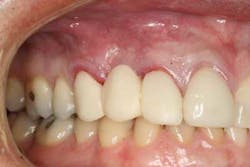

Immediately post-insertion, a periapical radiolucency was detected on the post-insertion radiograph on tooth No. 7 and the patient was immediately sent for root canal therapy. Four months was allowed for implant integration. At the time of Stage II, a noninvasive punch tissue technique was employed and a 3 mm healing abutment was placed. At the time of impression, an open tray technique was used and a custom abutment was selected. Because of the patient’s canine guidance occlusion, a porcelain-fused-to-metal crown was selected along with all-ceramic crowns on teeth Nos. 5 and 7.

One year post-insertion radiographs indicate that bone levels around the implant remain stable. Clinical results 1.5 years post-insertion reveal gingival levels to be stable and healthy, and the patient is very pleased with the esthetic result of his treatment.